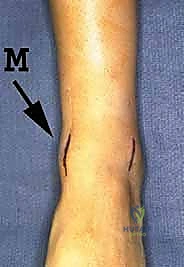

هو إحداث توازن مثالي بين الجراحة المفتوحة وجراحة المناظير. يقوم الأستاذ الدكتور محمد هطيف بإجراء الجراحة عبر شقين أو ثلاثة شقوق صغيرة جداً (لا تتجاوز 2-4 سم). من خلال هذه النوافذ الصغيرة، وباستخدام أدوات جراحية دقيقة ومخصصة، يتمكن من الرؤية المباشرة للمفصل، وإزالة الغضاريف التالفة بالكامل، وتجهيز العظام للدمج، ثم تثبيتها بالبراغي.